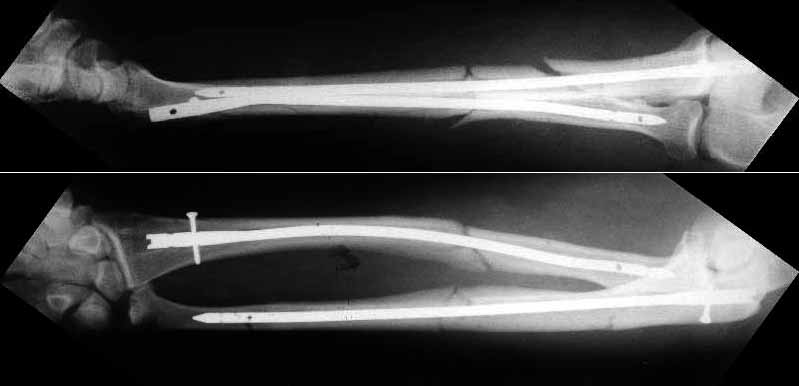

A male 51 years old admitted to our unit 4 days after industrial trauma (a heavy piece of metal fell on the forearm) already in a plaster cast. Swelling was so significant that compartment syndrome was expected but he still has been demonstrating good sensation and movement of fingers. Also there were 2 sites of skin necrosis 3x1 cm, with serous drainage. He was left in the plaster for a week - looks better now. Swelling decreased, no pus. What surgical option should be preferred? As i realize, primary alternatives are closed nailing and external fixation? THX in advance.

![]() |